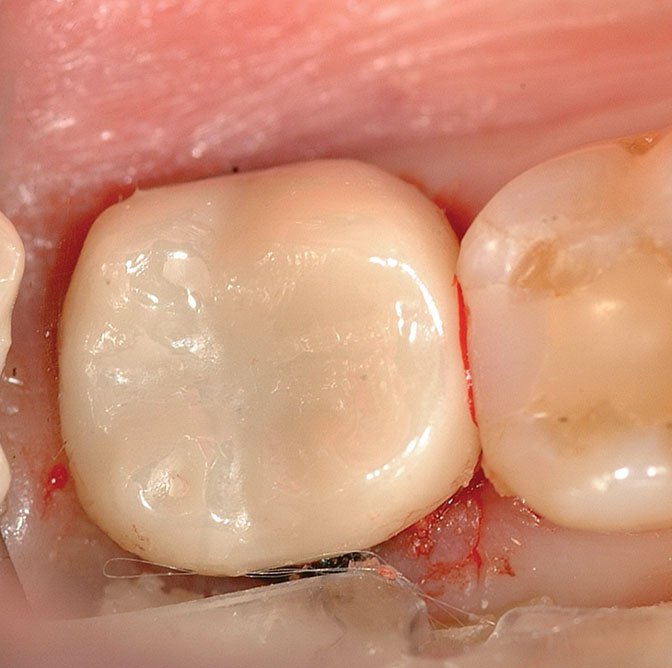

Post cementation cleanup

Post cementation cleanup.